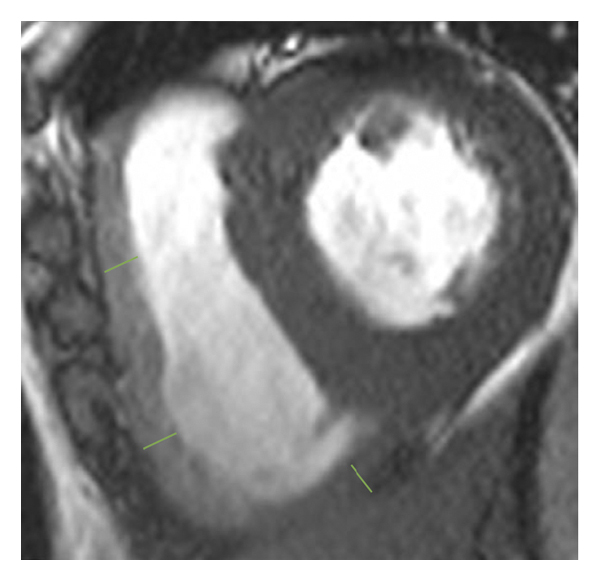

2.3. 이미징 분석모든 이미지 분석은 시중에서 판매되는 소프트웨어(cvi42, Circle Cardiovasic Imaging, Inc. Calgary, Canada)를 사용하여 수행되었습니다. 심장 기능을 측정하기 위해 심장내막 및 심외막 추적을 확장기 말기 및 수축기 말기의 직렬 단축 슬라이스에서 수동으로 수행했습니다. LV/RV 확장기말 용량(EDV), 수축기말 용량(ESV) 및 LV/RV 박출률을 포함한 전체 LV/RV 수축기 기능이 계산되었습니다. LV 및 RV 심근 스트레인 분석은 장축 4챔버 및 단축 슬라이스를 조직 추적 모듈에 로드하여 수행되었습니다(그림 1 (a) 및 1 (b)). RVT는 중실의 3회 측정하였고, 평균 두께를 계산하였다(도 1 (c) 및 1 (d)). GRPS(글로벌 라디칼 피크 변형), GLPS(글로벌 세로 피크 변형) 및 GCPS(글로벌 원주 피크 얼룩)를 포함하여 전역 특징 추적 매개변수가 자동으로 획득되었습니다. 최고 수축기 변형률(PSSR, 이완기부터 다음 수축기까지의 모든 단계에 대한 절대값의 최대 변형률)과 최고 확장기 변형률(PDSR, 수축기부터 다음 수축기까지 모든 단계에 대한 절대값의 최대 변형률)은 다음과 같습니다. 또한 분석했다. 양수 기호와 음수 기호는 서로 다른 동작 방향을 나타냅니다. 앞서 기술한 바와 같이[ 16 ], 정상적인 RVT 값은 7mm 이하로 정의되었다. 기준에 따라 CA 및 HCM 환자를 RV 비대(RVT >7 mm) 또는 RV 비대(RVT ≥7 mm) 환자에 따라 하위 그룹으로 나누었습니다.

(ㅏ) -

(비) -

(씨) -

(디)